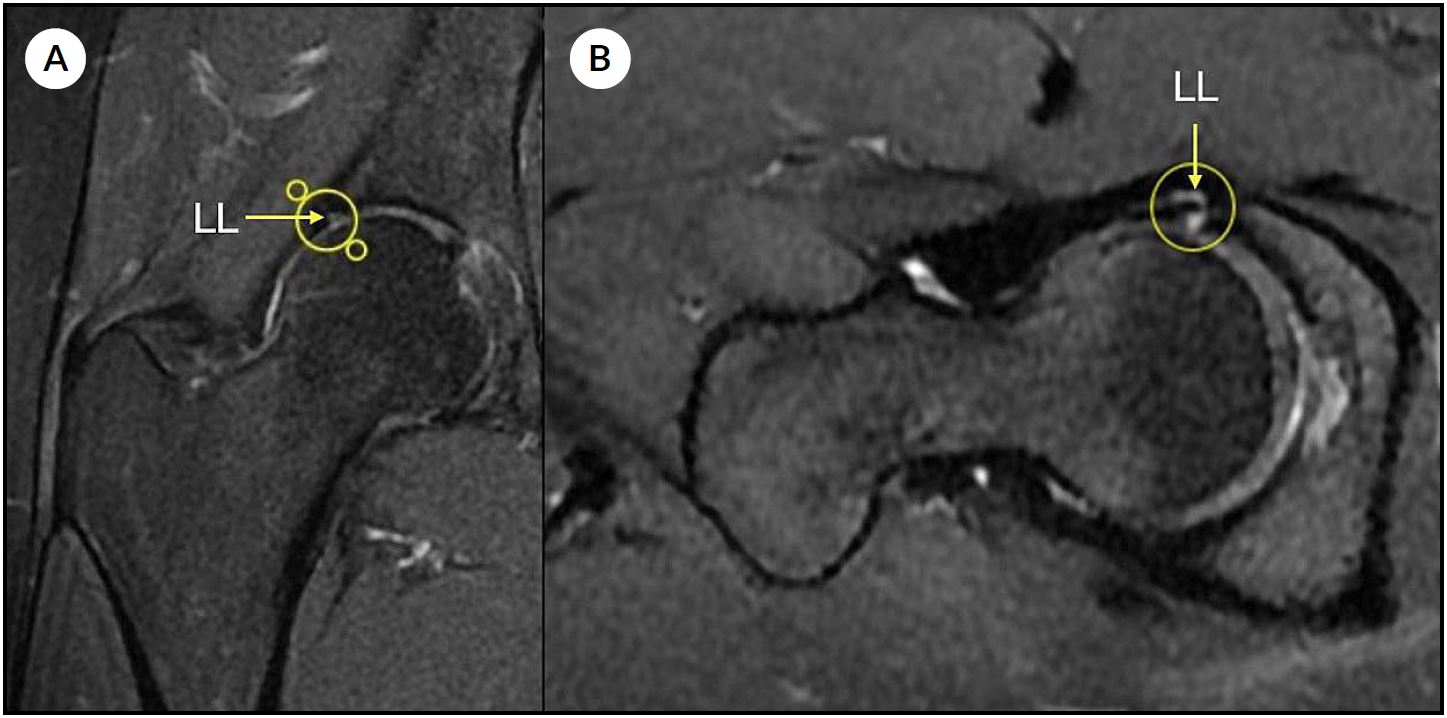

La evaluación por imágenes incluyó radiografías de pelvis anteroposterior, proyección de Lowenstein y de Dunn, resonancia nuclear magnética (RNM) de al menos 1.5 Tesla con cortes acetabulares radiales, y tomografía computada con reconstrucciones radiales para la evaluación detallada de deformidades femorales y acetabulares mediante mediciones angulares con distribución horaria. El punto de corte para el diagnóstico de displasia limítrofe fue un ángulo centro-borde lateral (LCEA de Wiberg) entre 20° y 25° (Fig. 1). La RNM fue utilizada para la detección de patología labral y/o condral asociada (Fig. 2). Las características demográficas y clínicas de la muestra se detallan en la Tabla 1.

Figura 2. Resonancia magnética de cadera (Secuencia T2). A) Corte coronal que evidencia lesión labral (LL) anterosuperior. B) Corte axial en el que se identifica lesión labral (LL). La flecha y el círculo en ambas imágenes señalan el área de lesión.